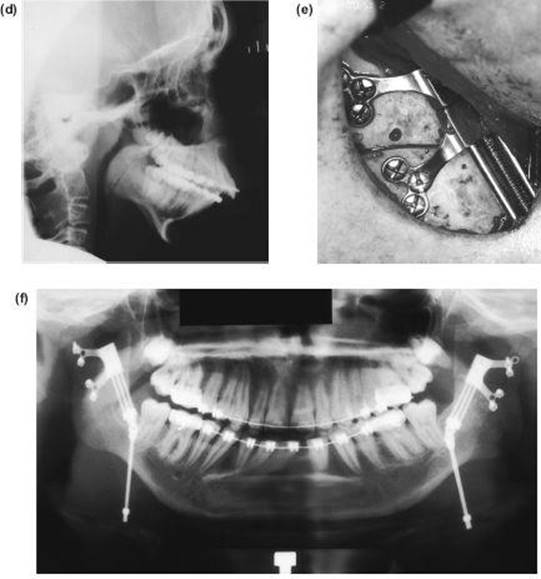

This operation is valuable when there is a need to increase both the ramus height and body length at the same time, especially when the sagittal split osteotomy is not possible. Such cases are usually gross congenital mandibular hypoplasia or, occasionally, acquired hypoplasia following condylar fractures or when previous surgery has disturbed the bony anatomy. The operation differs in concept from the sagittal split procedure in that a bone graft is inserted to make up the deficiency.

Technique

1. The surgical approach is exactly the same as for the extraoral subsigmoid osteotomy (steps 1-6 and see Figure 9.4) except that the bone cut is made from the anterior border of the ascending ramus, passing distally, to behind the estimated position of the lingula then downwards to the lower border anterior to the angle, i.e. to the antegonial notch (Figure 9.7a).

4. With the proximal condylar fragment confirmed to be in the fossa, the gap created can be measured, and a template formed with sterile paper or card.

Figure 9.7 (a), (b)

5. An interpositional graft is now obtained. The ideal source is cortico-cancellous bone from the iliac crest. A solid cancellous graft can be used but the incorporation of one cortex provides reassuring stability. Some surgeons use split rib for the gap. Two miniature bone plates provide excellent rigidity and form (Figure 9.7b).

6. A vacuum drain is inserted and the wound is closed in layers.

7. The intermaxillary fixation is released and the pack removed.

Note: Any mandible which requires lengthening with an inverted L osteotomy also requires an augmentation genioplasty.